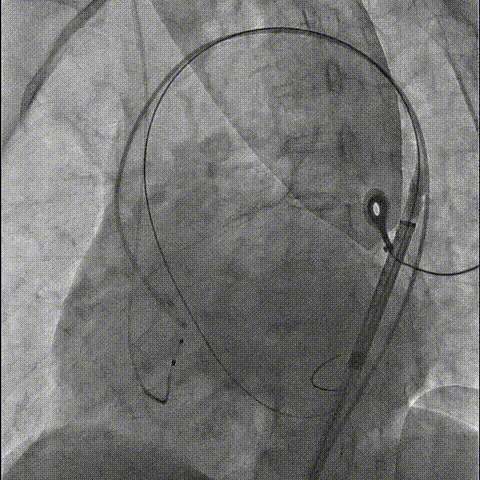

初始定位及释放

释放中评估

完全释放